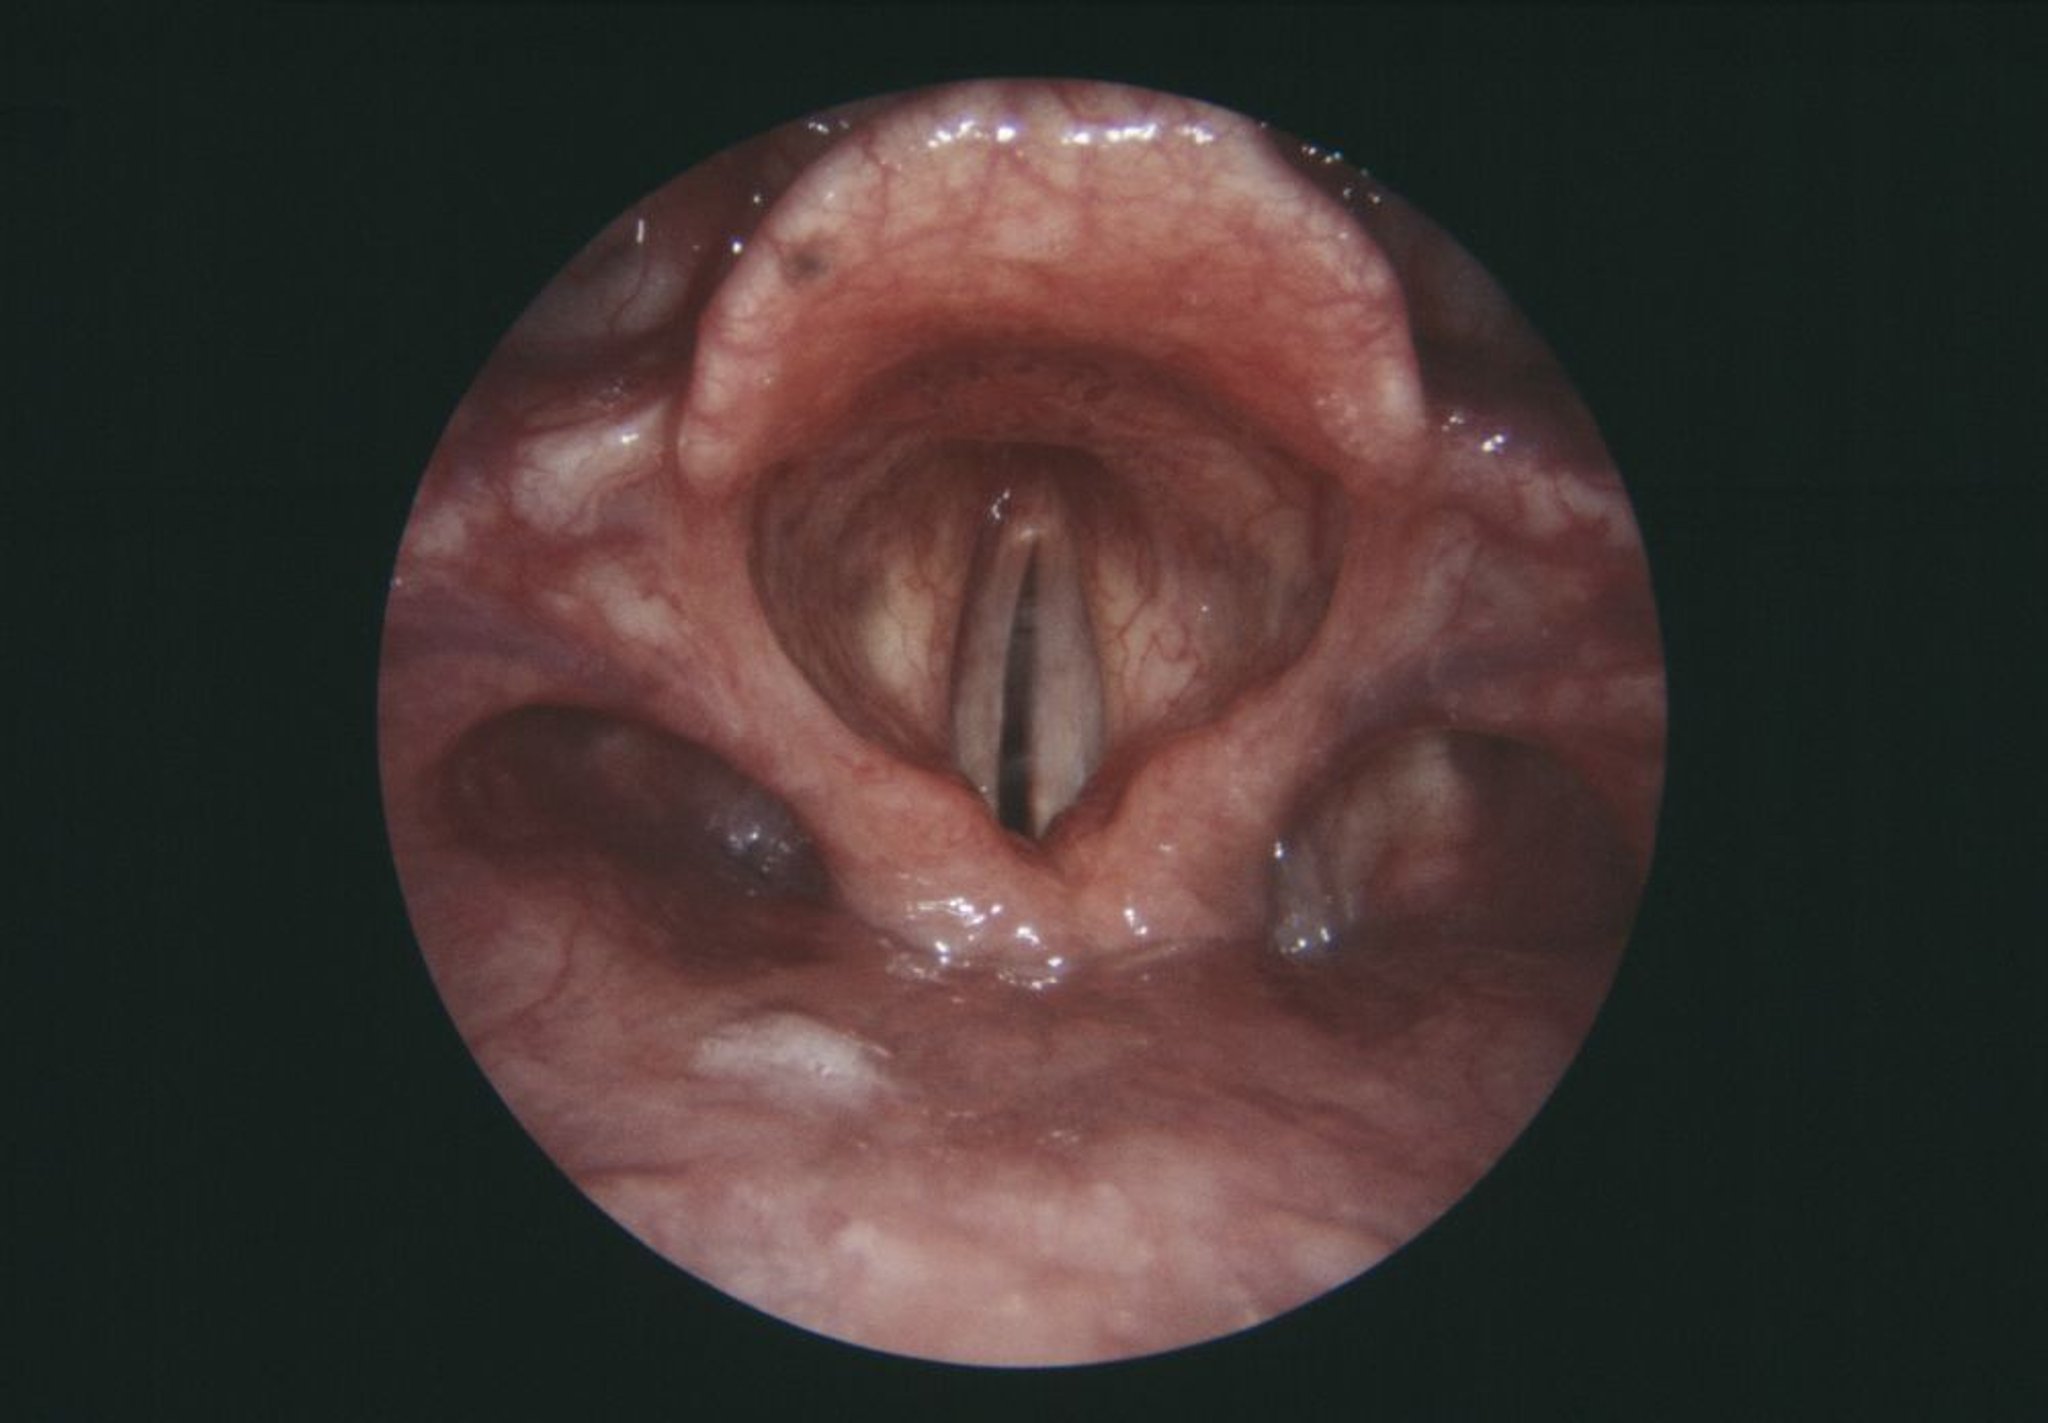

Parálisis de las cuerdas vocales

Esta vista endoscópica de la laringe muestra una cuerda vocal derecha paralizada (en color gris, centro izquierda).